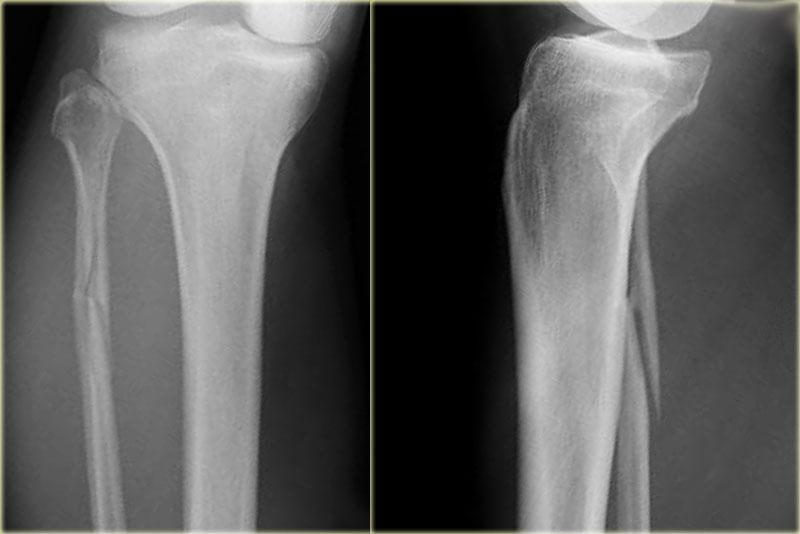

Stage 1

Các hình ảnh cho thấy gãy xương loại Weber A điển hình.

Tất cả đều là gãy xương giai đoạn 1.

Giai đoạn 2 cực kỳ hiếm gặp.

Chú ý hướng nằm ngang của các đường gãy.

Đây là các gãy xương kiểu giật đứt do kết quả của sự bong gân giật.

Stage 2

Giai đoạn 2 không phổ biến và dễ phát hiện.

Lực khép lớn hơn dẫn đến mắt cá trong bị đẩy ra theo chiều dọc hoặc chéo.

Giai đoạn 2 không vững vì vòng cổ chân bị gãy ở hai vị trí.

Lưu ý hướng nằm ngang của gãy mắt cá ngoài và hướng thẳng đứng của gãy mắt cá trong.

Những lực cực lớn hẳn đã đẩy bật mắt cá trong ra.